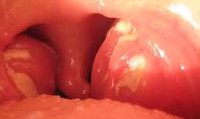

Лакунарная ангина у детей протекает с наличием линейного гнойного налета желтоватого цвета, расположенного в лакунах между долями миндалин. Поверхность миндалин ярко гиперемирована и отечна; островки налета в устьях лакун склонны к объединению и образованию широких сливных гнойных очагов. При микроскопическом исследовании обнаруживаются множественные изъязвления эпителия, лейкоцитарная инфильтрация слизистой, гнойное расплавление фолликулов, тромбозы мелких сосудов.

Фарингоскопия у детей определяет разлитую гиперемию миндалин и дужек, инфильтрацию, наличие налета, характер которого позволяет судить о клинической форме ангины. Гнойный налет при ангине легко снимается шпателем, растирается по стеклу и не оставляет кровоточащей поверхности (в отличие от трудноудаляемого налета при дифтерии).